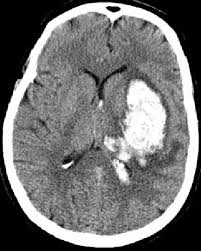

Brain scan: Black = ischemic stroke, white = hemorrhagic stroke. Source

Chronometric age of the brain lesion is a critical parameter clinicians use to assess the types of interventions a patient may benefit from receiving. The best contemporary method for treating acute stroke, administering tissue plasminogen activator (tPA) to break blood clots in the brain, is only effective within the first 4.5 hours post-stroke. Similarly, surgical interventions have been shown to be more effective in the first 6 hours post-stroke compared to 6-24 hours post stroke.